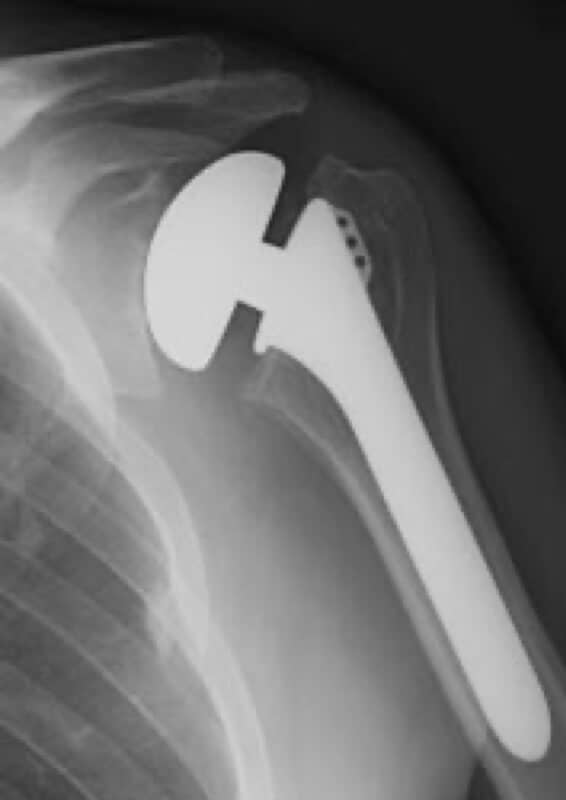

Stryker/Wright/Tornier, Solar Bipolar